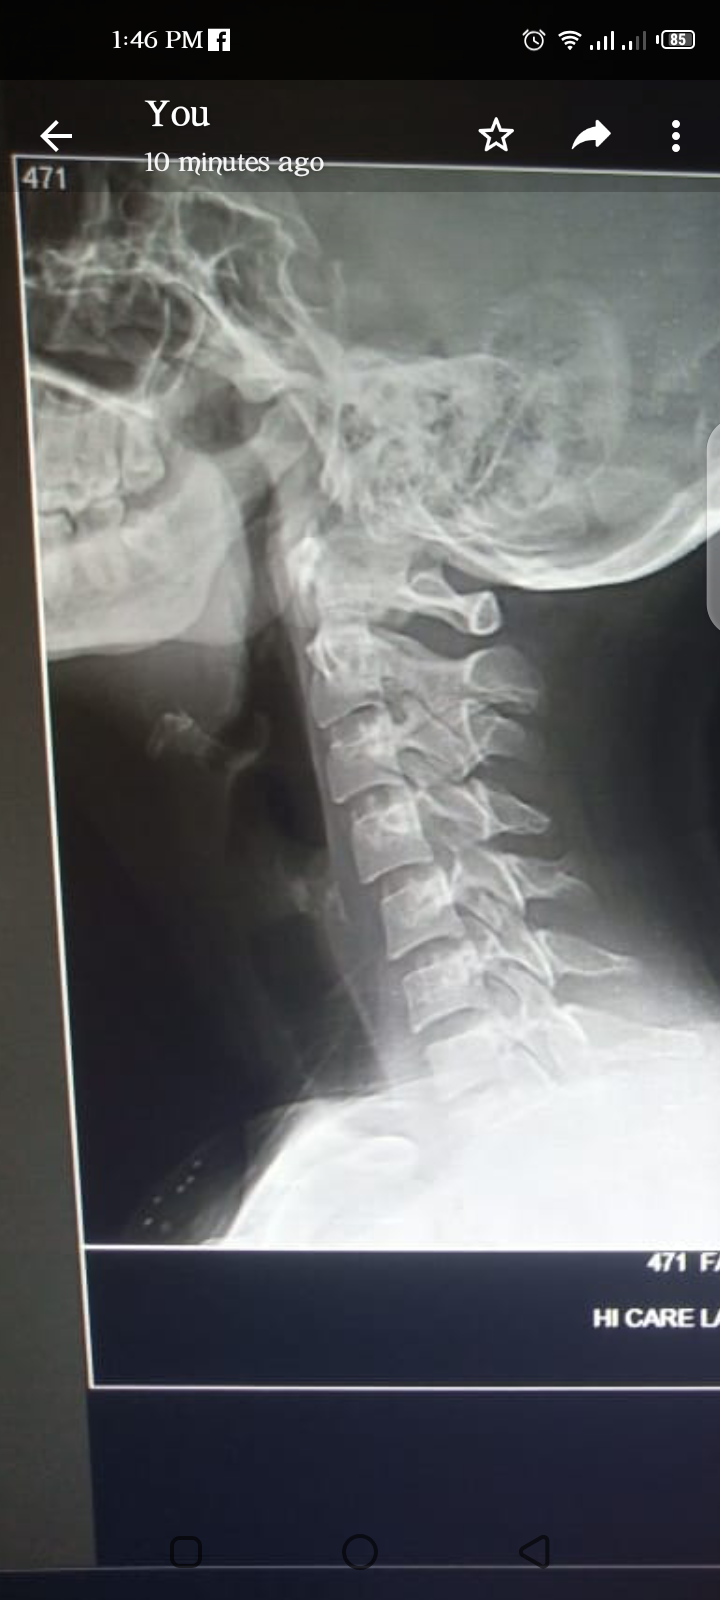

4 mnth ho rahy han muscular spasm nhi jara bht medicen use kar li nhi arha faraq. Cervical prblm bhi hora ha kafi drs ko dikha choki hu aab na umeed hori hu pls help kya karo kha jao theek hojao.. Ahista ahista poray body k muselc tyt horahy han

Attach Photo here: